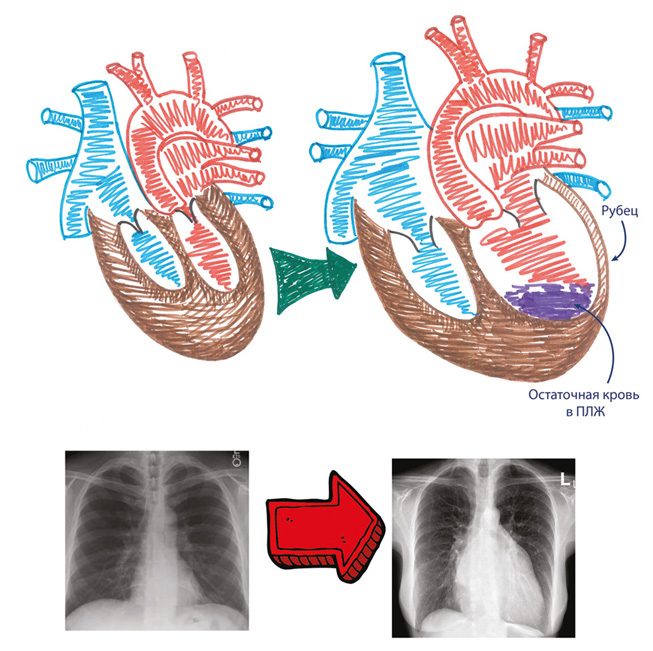

Ремоделирование сердца после инфаркта

Иллюстрация к книге — Как жить после инфаркта [i_020.jpg]